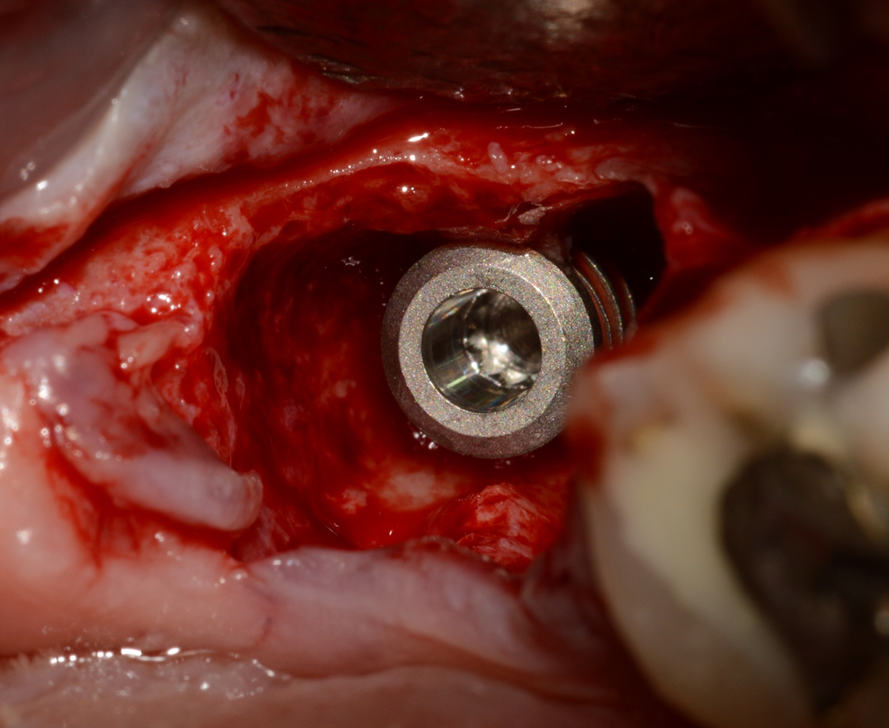

A sequência de imagens a seguir apresenta casos da aplicação clínica do Extra Graft em cirurgias de exodontia e implante imediato com preenchimento dos gaps, e apenas exodontia e preenchimento alveolar para favorecer a regeneração óssea.